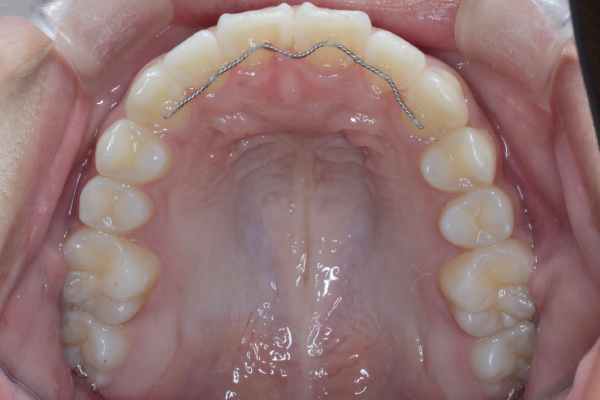

検査の結果、歯列全体のスペースバランスを調整することで、抜歯を行わずに歯並びの改善が可能と判断しました。歯の移動量やコントロール性を考慮し、今回はワイヤー矯正を用いた治療計画をご提案し、患者様にも十分ご理解いただいた上で治療を開始しました。

10代での叢生は、見た目の問題だけでなく、将来的な虫歯や歯周病のリスクにもつながることがあります。この患者様のように、成長期のタイミングで適切に矯正治療を行うことで、歯や噛み合わせを良い状態で長く保つことが期待できます。

約2年間にわたる矯正治療は決して簡単なものではありませんでしたが、最後までしっかり通院していただき、良好な歯列を獲得することができました。今後は後戻りのチェックとともに、定期的なメンテナンスと虫歯予防を継続していくことが大切です。